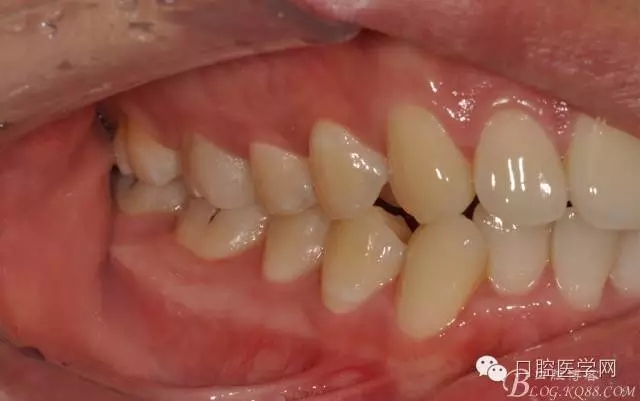

圖15 術(shù)后連續(xù)側(cè)方位咬頜觀